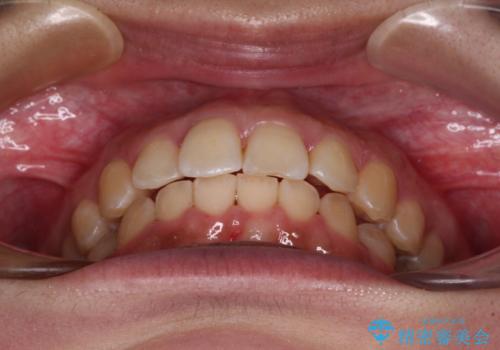

前歯のデコボコをインビザライン矯正で綺麗に改善

- 上下前歯のデコボコを気にして来院された患者様です。

全体的に叢生は軽度であったため、インビザラインにて矯正治療を行うこととしました。

舌の突出癖改善がうまくいかず、途中で舌小帯の切除を行いました。

気になる段差を納得いくまで改善させたため、治療期間は長くなりましたが、綺麗な仕上がりとなりました。